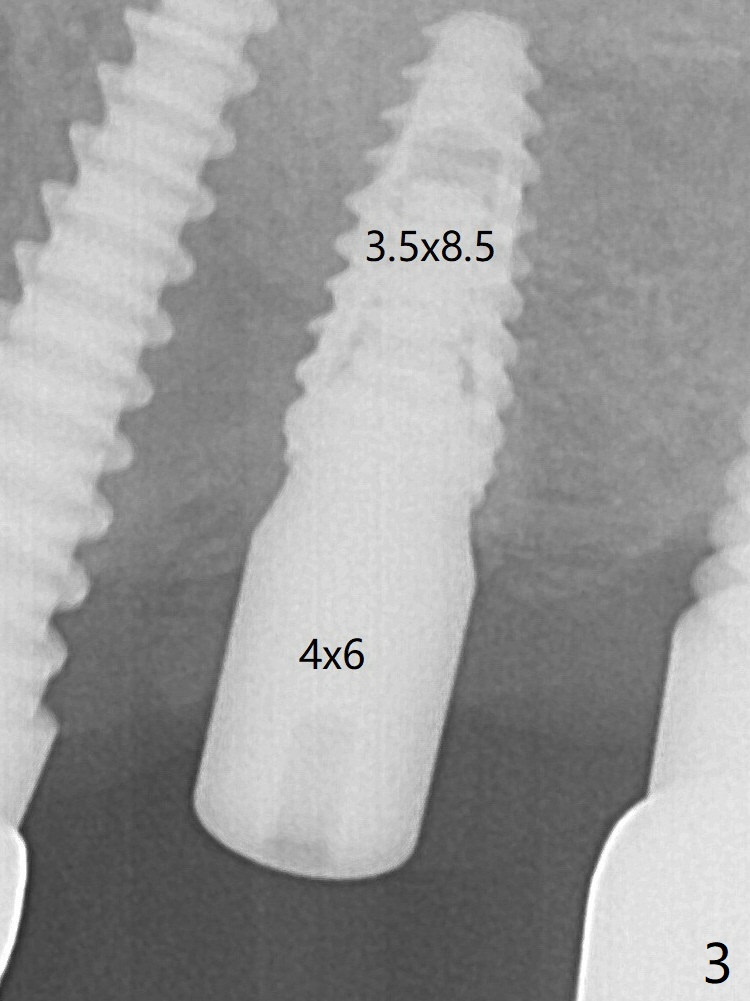

A 4x6 mm healing abutment is inserted (Fig.3).  There is crestal bone loss 6 months postop (Fig.10 arrowheads).